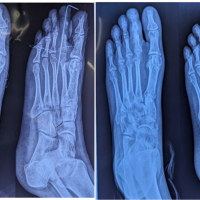

An X-ray of the hand showed a radiopaque mass of 5.0 × 4.5 cm with slight internal calcification on the palmar side of the fifth proximal phalanx, without changes in the bony cortices, additionally lytic image in the proximal third of the middle phalanx of the fifth finger with sclerotic borders, polylobulated pattern, without periosteal or soft tissue reaction (Fig. 2).